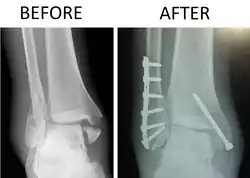

X-ray of trimalleolar fracture repair before and after ORIF surgery

A trimalleolar fracture is a fracture of the ankle that involves the lateral malleolus, the medial malleolus, and the distal posterior aspect of the tibia, which can be termed the posterior malleolus. The trauma is sometimes accompanied by ligament damage and dislocation.[1]

Surgical repair using open reduction and internal fixation is generally required, and because there is no lateral restraint of the foot, the ankle cannot bear any weight while the bone knits. This typically takes six weeks in an otherwise healthy person, but can take as much as twelve weeks. Non-surgical treatment may sometimes be considered in cases where the patient has significant health problems or where the risk of surgery may be too great.[1]